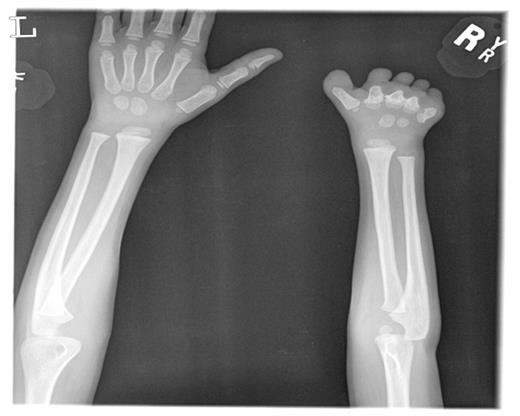

We describe a 2-year-old child with an incidental finding of persistent elevated platelet count. The platelet count at the time of referral was 900 × 109/L. His physical examination revealed bony abnormalities of the right upper extremity, and hand. (Photo1) X-Ray of the hand revealed amputation of the fingers of the right hand with rudimentary metacarpal bones, and evidence of shorter radius and ulna of the of the left forearm when compared to the right. The physical examination was otherwise normal with the exception of moderate splenomegaly. Further workup revealed normal iron stores, and no inflammatory process which could explain the thrombocytosis. Chromosomal breakage and rearrangements studies were normal and confirmed a normal male karyotype. A bone marrow aspirate and biopsy revealed megakaryocytic hyperplasia with many binucleated and trinucleated megakaryocytes. (Photo 2) The erythroid and myeloid series were well represented and of normal morphology. Flow cytometry for ALL specific and CMLspecific markers were normal. The platelet count reached 2,800 × 109/L, and serum thrombopoietin level was obtained, which returned 2119.8 pg/ml. The patient was placed on hydroxyurea and aspirin 81mg/day, and reduction in the platelet count occurred. After six months of hydroxyurea therapy the platelet count rose again to pretreatment levels. Hydroxyurea was discontinued and anagrelide started with moderate platelet reduction. Family members were also evaluated. The siblings all had normal platelet counts but the mother had an elevated platelet count 900 × 10 9/L. The bone marrow aspirate of the childs mother was also consistent with ET. The JAK2 kinase mutation was not found in the mother or the child. The childs mother was also found to have an elevated thrombopoietin level of 475.6 pg/ml and was started on hydroxyurea.